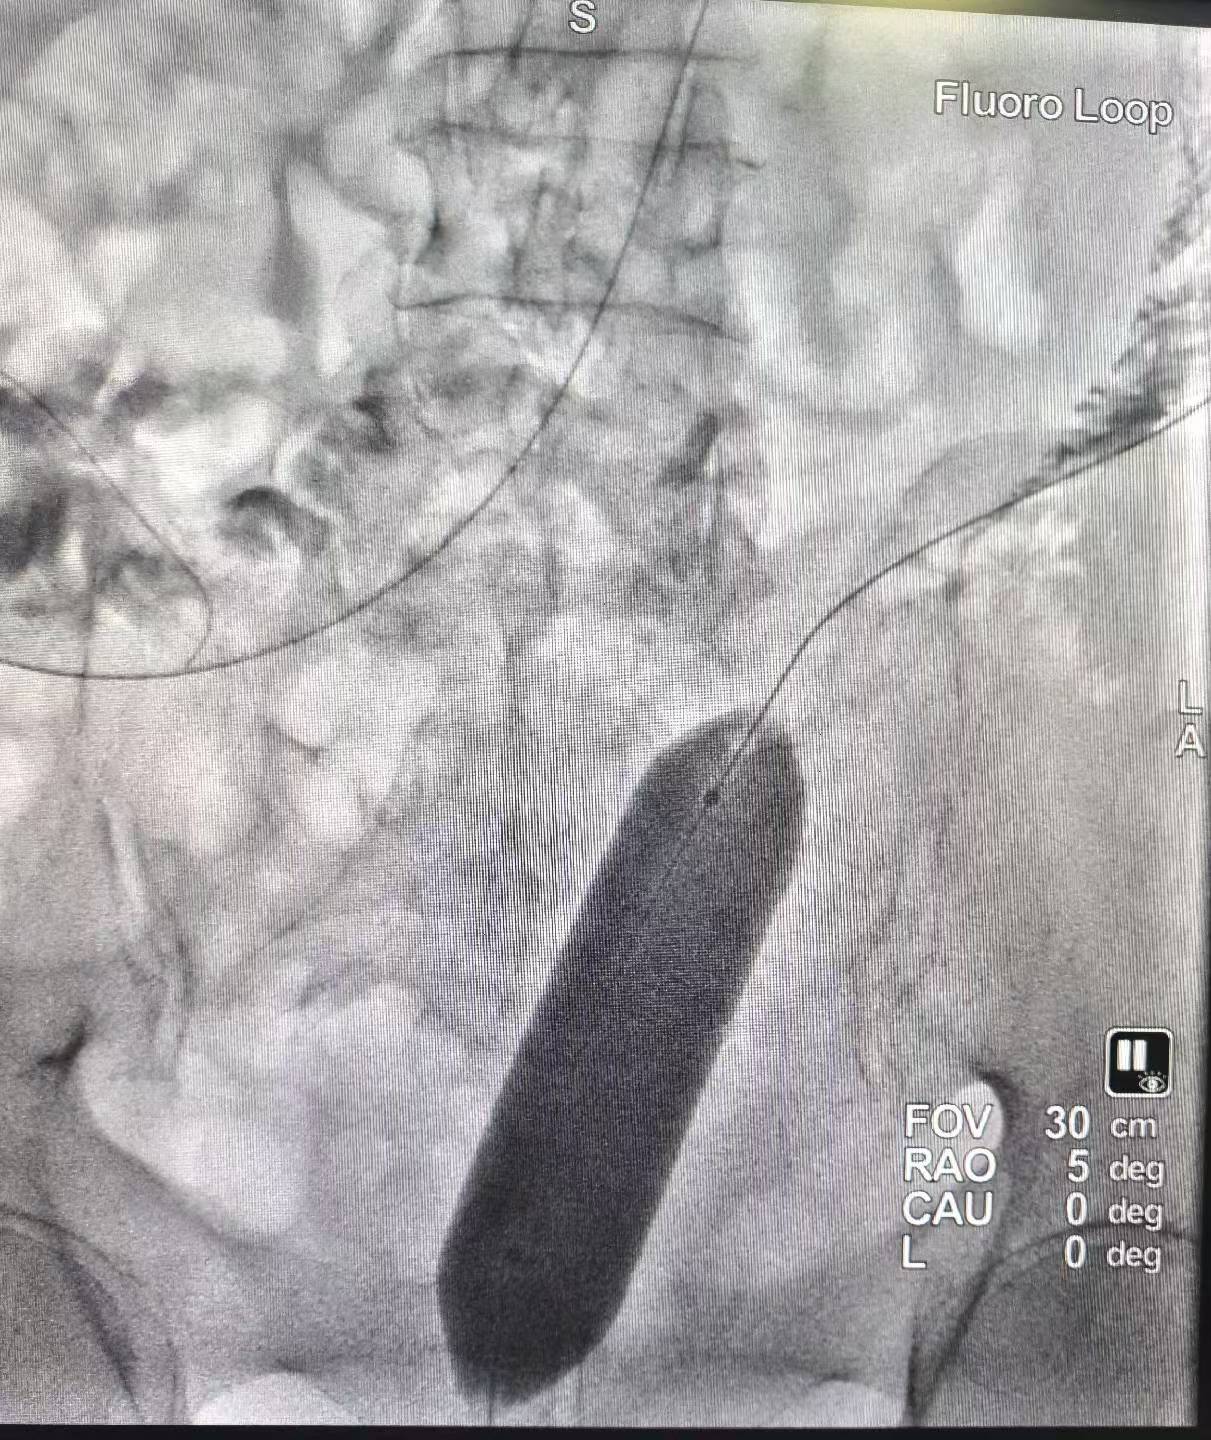

直肠癌术后吻合口狭窄(难治型)球囊扩张术。上午一台直肠癌术后吻合口狭窄经肛行球囊扩张术,球囊充分扩张后狭窄解除。介入球囊扩张对良性难治性狭窄,安全有效,术后即可排便顺畅。